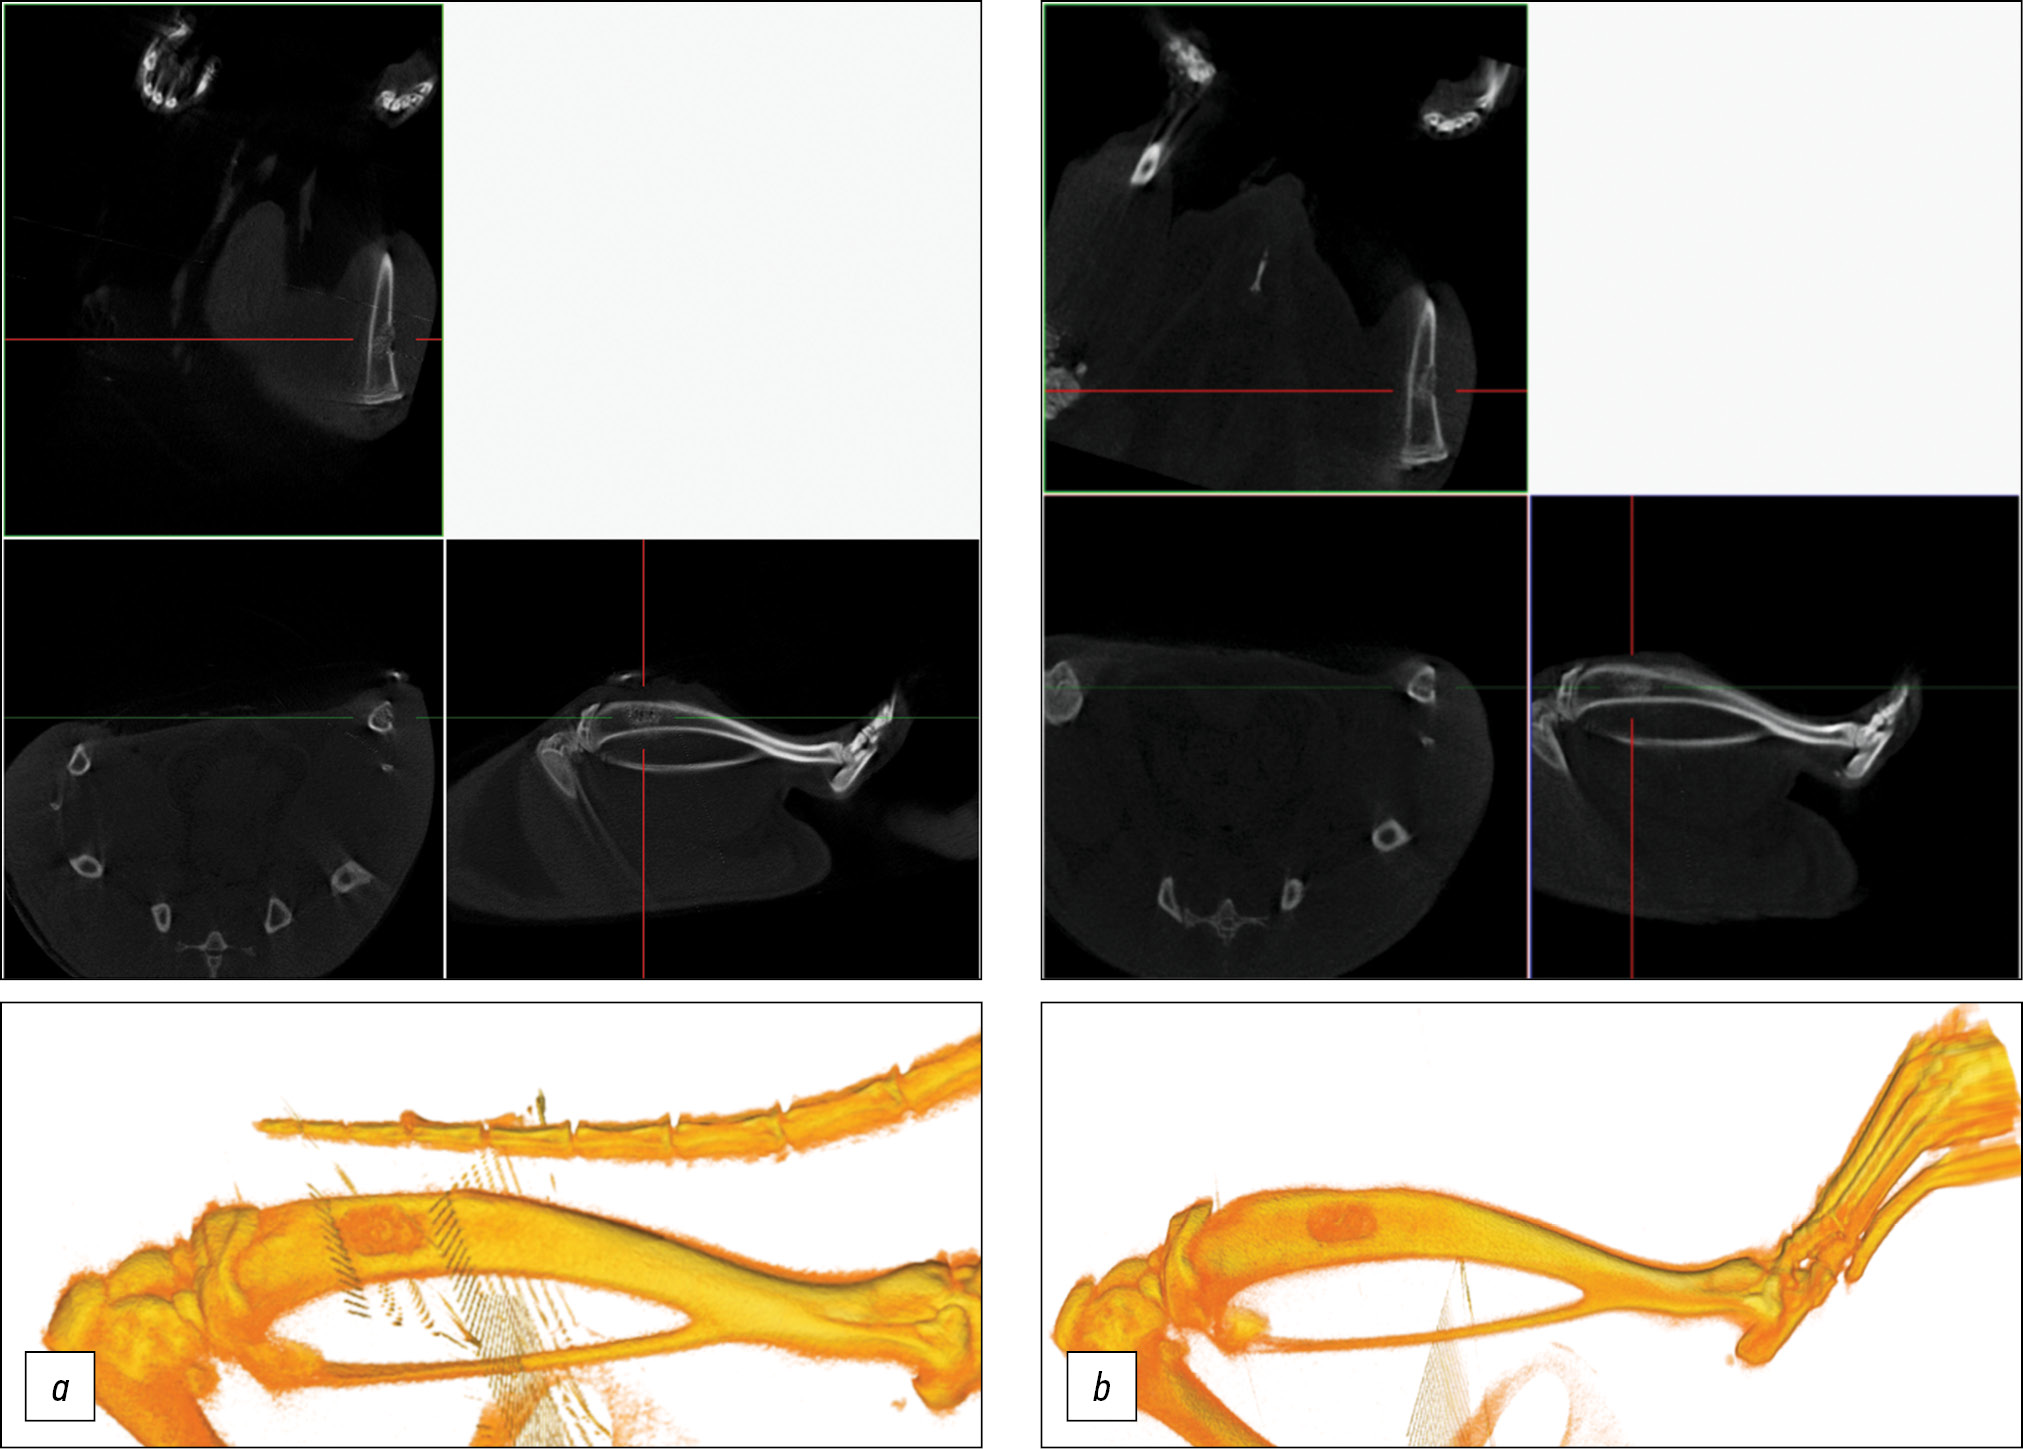

A micro-CT was conducted in vivo after surgery and postmortem at 2 weeks and 1 month after implantation. Micro-CT was performed using a Bruker SkyScan 1178 scanner (Kontich, Belgium) with a voltage of 65 kV and a current of 615 μA, and a 0.5 mm A1 filter was used. The spatial resolution was 84 μm/pixel. The sections were reconstructed using NRecon software, version 1.6.10.4, and 3D reconstructions were performed using CT Vol 2.2.0.0 program.

based on microtomographic and histological studies, no macroscopic changes in the trabecular bone structure were observed after exposure to our cleaning protocol. This is supported by the results of the tomographic study (Fig. 2). The bone trabeculae form a cellular network of normal cancellous bone, as shown in the histological study (Fig. 3). The bone matrix has a normal thin-fiber structure. According to the results of the tomographic study (Fig. 2), the clearance factor of the xenogenic bone matrix was approximately 0.91±0.05. Table 1 presents the proposed screening method based on micro-CT by the density range for the substance/tissue, which provides a quick assessment of the degree of clearance of the intertrabecular space. Although this method is coarse and cannot be used as the only control method, it is the least labor-intensive and fastest and can be applied for primary screening in the purification process.

Fig. 2. Results of tomographic examination: a — 3D reconstruction, b — micro-CT slice.

Based on CT data, the model of bone perforation in in vivo experiments showed that after implantation, the material adhered tightly to the bone walls and was located in the bone defect area, without any migration (Fig. 5). After 14 days, the material remained visible in the projection of the defect; however, partial resorption was observed. The area of the defect decreased, and regeneration formation from the bone edges was observed. No radiologic signs of inflammation were found. After 30 days of implantation, the material was observed in the projection of the defect, and significant resorption of the material was determined. It was mainly preserved in the medullary canal (Fig. 6). The defect area significantly reduced, and a pronounced bone callus with formed bone bridges running along the surface of the implanted material was noted.

Fig. 5. Orthogonal projections and 3D model of the rat tibia: a — at the time of implantation, b — after 14 days.